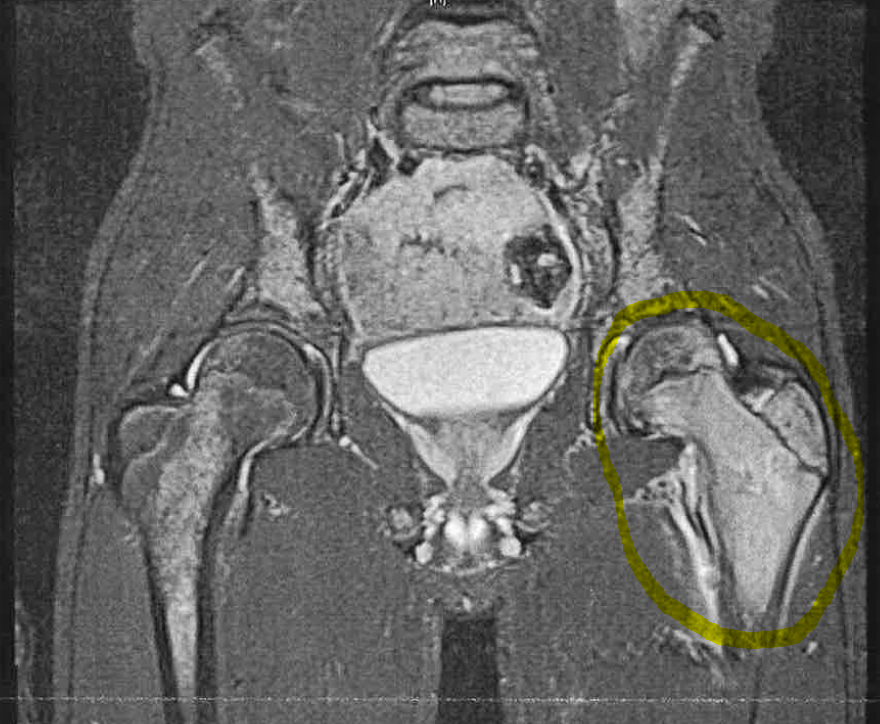

We are are being asked a lot where is his cancer.  It is basically all over….it’s not something they can surgically remove.  The surgery today is to get a piece of his femur bone to send to a lab to see what chemo he needs.  They will also be doing a bone marrow biopsy on both hips and placing a port in his chest.  The purpose of the port is so when he gets medicine at a later date they do not need to constantly stick him with needles.  They just access the port.